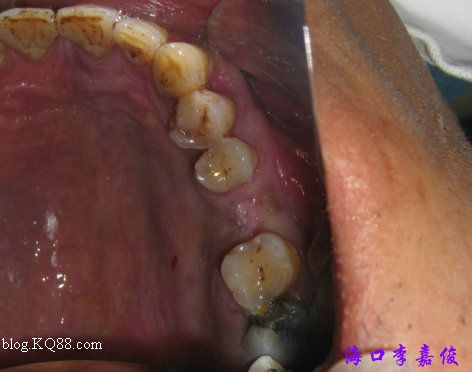

下牙牙齦菲薄